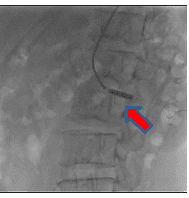

経皮的末梢動脈形成術の一例

- 【1】術前

-

- 【2】ワイヤー通過

- 【3】ステント留置

- 【4】術後